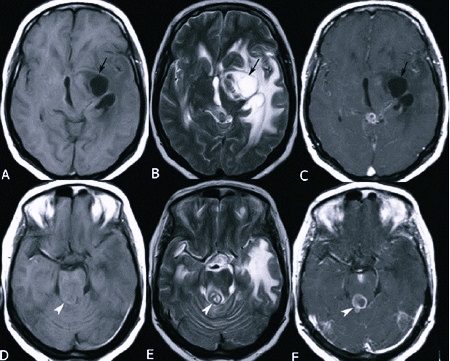

- Компьютерная томография (КТ) – послойное сканирование тканей, при котором визуализация происходит при помощи рентгеновских лучей. Методика обладает высокой разрешающей способностью и позволяет выявить мелкую псевдокисту, песок в полостных образованиях.

- Магнитно-резонансная томография (МРТ) – метод подразумевает послойное сканирование, при котором визуализация тканей осуществляется при помощи физического эффекта резонанса ядер в сильном магнитном поле. Исследование нельзя проводить при наличии металлических имплантатов у взрослого человека или ребенка.

Выбор методики исследования осуществляется лечащим врачом индивидуально. При помощи проведенной диагностики определяется характер образования (субэпендимальный тип, истинная киста), его локализация (справа или слева по отношению к срединной линии), а также размеры. Это дает возможность выбрать оптимальную терапевтическую тактику.